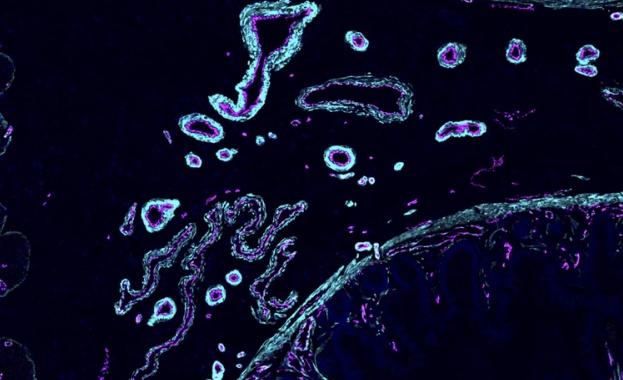

Човешките клетки могат да "чуват", установиха учени

/КРОСС/ Учени от Университета на Киото, Япония, са установили, че звукът се възприема не само от ухото и мозъка, но дори отделни клетки на тялото реагират на него, пише Физ.орг, позовавайки се на публикация в сп. "Къмюникейшънс байолъджи".

Звукът представлява механични вълни, които се разпространяват във въздуха. Той е в състояние да предава важна информация за заобикалящия свят и да предизвиква различни физиологични реакции. Едва сега обаче учените започват да осъзнават, че акустичното налягане може да има пряко въздействие върху клетките на човешкото тяло.

За да провери тази хипотеза, екип, ръководен от Масахиро Кумета, е направил експеримент, при който клетки са били култивирани в условия на акустична стимулация.

С помощта на секвениране на РНК, микроскопия и други техники учените са анализирали поведението на клетките, когато са изложени на звук в чуваемия диапазон. Резултатите са поразителни - оказва се, че клетките наистина реагират на звук.

Особено забележим е бил ефектът на потискане на диференциацията на адипоцитите - процеса на превръщане на предшествениците на мастните клетки в зрели мастни клетки. Това открива възможности за използването на звука като безопасен и неинвазивен метод за управление на състоянието на тъканите.

Изследователите освен това са идентифицирали

около 190 чувствителни към звука гени, регистрирали са промените в тяхната активност и са проучили вътреклетъчните механизми на предаване на звуковия сигнал.

Звукът е нематериален, но мощен инструмент. Той е безопасен, не изисква намеса и може да се използва за целенасочено регулиране на физиологичните процеси, отбеляза Масахиро Кумета.

В бъдеще учените планират да изследват по-задълбочено ефектите на звука върху клетките и да използват получените знания за медицински цели.